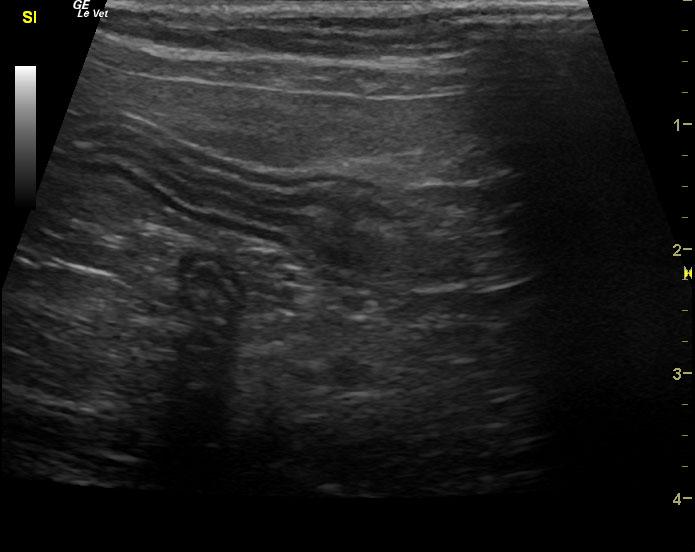

An 18-year-old MN DMH was presented for evaluation of intermittent vomiting and anorexia. A possible abdominal mass was present on abdominal palpation. 1+ calcium oxalate crystals were present on urinalysis. Abnormalities on CBC and serum biochemistry were leukocytosis and hypoproteinemia. T4 was within normal range. Radiographs were within normal limits